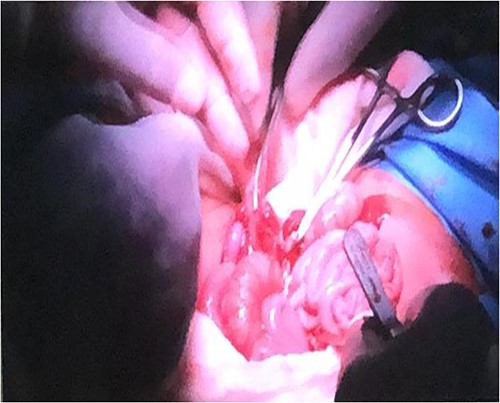

Following the placement of central lines, the two babies were anathesized and stabilized with vital sign monitoring and fluid adjustments. Then, using monopolar and bipolar diathermy, incisions and flaps were made until the peritoneum, where complete fusion of the liver with a sinusoidal connection was discovered. The connected surface area is ⁓8 by 6 cm, primarily in the caudal lobe, whereas twins B has one lobe liver and one gall bladder (Fig. 4). The xiphoid process, sternum, pleura and pericardium were all visible in the patient and were successfully separated. To avoid the occurrence of compartment syndrome, the abdomen was left as a shallow cavity with only skin closed as a neonatal hernia, then hemostasis was secured via PDS sutures and drains were placed, admitted to neonatal intensive care unit and received blood and fresh frozen plasma. The patients recovered well from anesthesia on the second day, were taken off mechanical ventilation with normal vital signs, and began Nasogastric tube tube feeding 48 h later. Patients began to gain weight and were discharged the next day to be seen at a referral clinic.